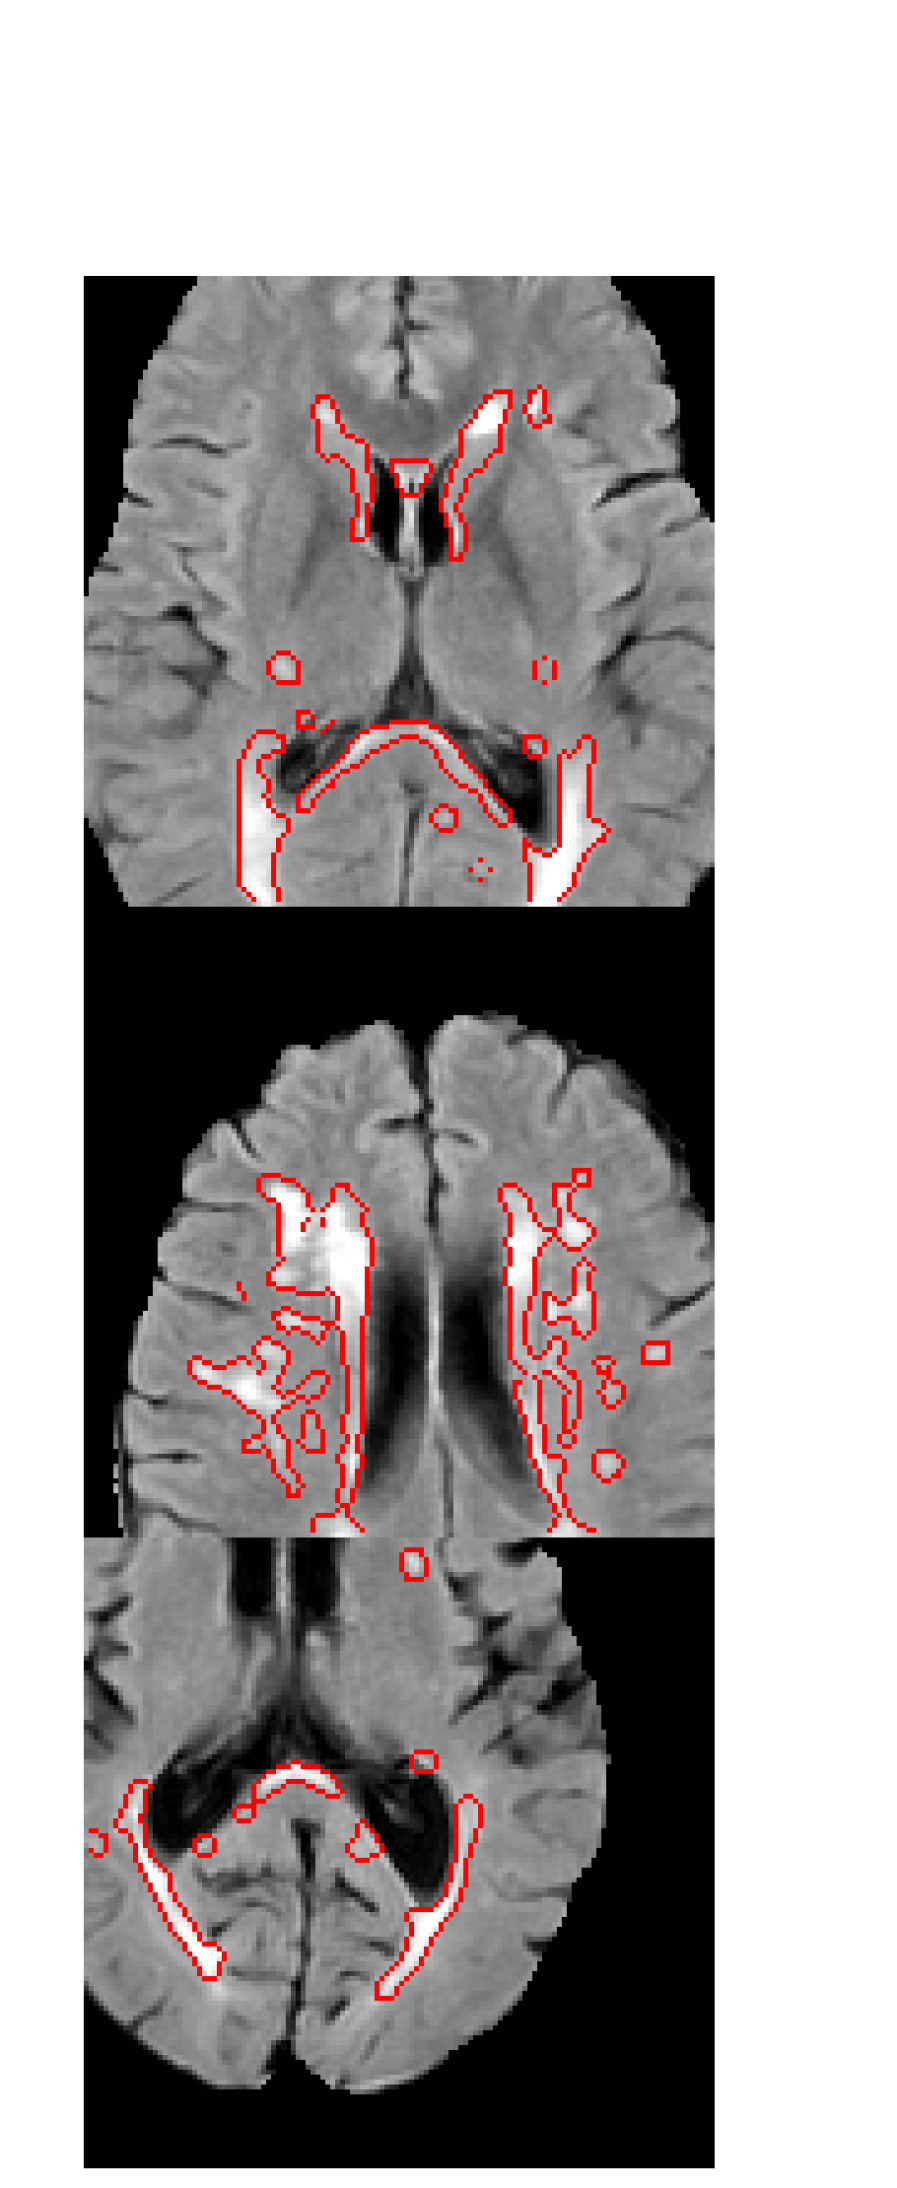

As well as the quantitative segmentation results, the generated MR images were also compared to their nearest neighbour in the training set to elucidate what extra information GAN augmentation provides. These images, a subset of which are shown in Figure 3, were examined looking for cases where: lesions were duplicated on different anatomy; lesions were changed whilst anatomy stays the same; the nearest neighbour is substantially different. The latter indicates the GAN has learned a smooth manifold leading to potentially novel anatomy.

Refer to caption

(a) 5 training images

(b) 25 training images

(c) 50 training images

Figure 3: Synthetic images (top of pair) with their nearest neighbours in the training set (bottom of pair) from GANs trained on patches from 5, 25 and 50 real MR images. Some local signs of successful augmentation are indicated using green (same lesions, different anatomy) and yellow (same anatomy, different lesions) arrows, and novel images (new anatomy and lesions) are shown with blue dots.

Figure 3 provides an interesting insight into what additional information is being provided by GAN augmentation. In the case of 5 training images, it is clear that each generated image is based heavily on an image from the training set. This is unsurprising as there are very few images to train on, and little variation which can be learned. However, there are subtle differences present in the majority of synthetic images. There are cases where lesions present in the real image are not reproduced in the synthetic image, as well as cases where the shape and number of lesions present in the synthetic image differ from those in the real image. Both of these effects can be extremely valuable to prevent overfitting when training a model - the former decoupling the presence of lesions from the surrounding anatomy, and the latter providing more variety of pathology. When the number of training images increases to 25, we begin to see cases where there are no close matches in the training set, in addition to the cases of differing anatomy and pathology seen previously. This trend gets even stronger in Figure 3 where all 50 training images are used. There are often substantial differences between the synthetic images and their closest real image, suggesting that the GAN has learned to produce data substantially beyond what was provided to it. We also observe that these modifications appear reasonable in all cases, with no obvious unrealistic lesions or anatomy being synthesised.